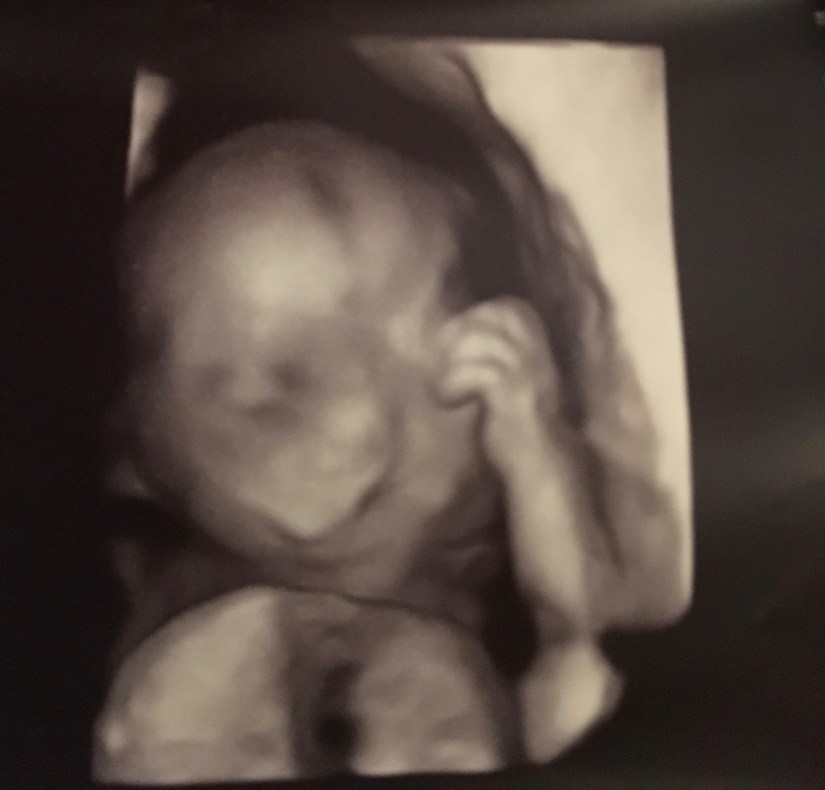

I was okay the rest of the appointment. Baby was measuring big still, we were still dealing with the poly, but otherwise, she looked good. No news is good news, right?

We had another ultrasound 3 weeks later and they set my induction date for 39 weeks. I defied all the odds (my odds) and lasted til my induction date!